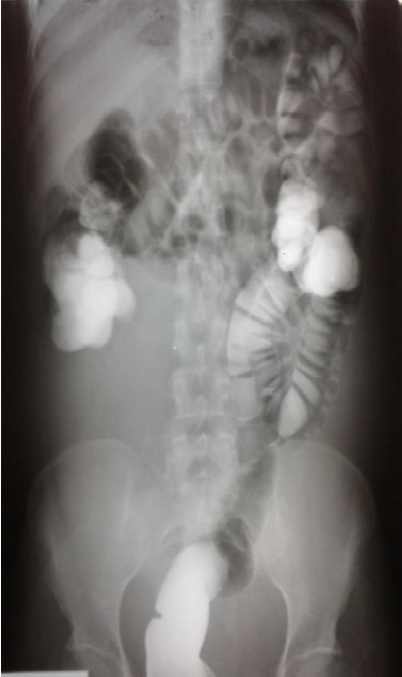

Colon por enema: al realizar Rx simple se evidencia inadecuado patrón de distribución del patrón neumofecal (figura 1), con desplazamiento de asas intestinales hacia hemiabdomen superior y flanco izquierdo por probable compresión extrínseca debido a lesión ocupante de espacio.

Se procede a realizar estudio contrastado con sulfato de bario por sonda rectal evidenciando adecuada plenificación del marco colónico en todos sus segmentos, con desplazamiento de asas intestinales por masa radio opaca que ocupa fosa iliaca derecha y fosa pélvica. Se diagnostica: Lesión ocupante de espacio en fosa iliaca derecha y fosa pélvica que condiciona desplazamiento de asas intestinales y Dolicocolon.

Se evidencia desplazamiento de asas intestinales por masa radio opaca que ocupa fosa iliaca derecha y fosa pélvica.